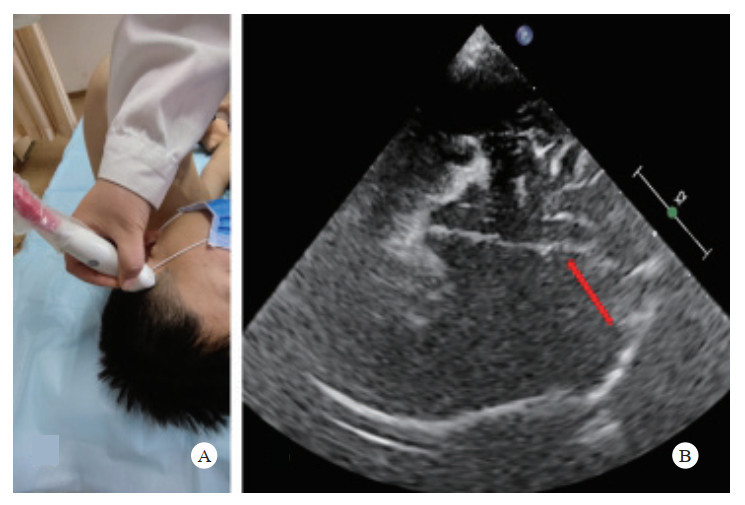

检查方法:采用高频(5.0~10.5 MHz)线阵超声探头。取仰卧位,头保持正中位,双眼睑闭合,眼球尽量固定。探头轻轻地放在闭合的眼睑上,避免过度施压。扫描切面分为横断面和矢状面。调整增益使视神经及其周围组织显示更加清晰。通常选择在眼球后3 mm的位置测量ONSD,测量时与视神经鞘的长轴垂直[27](图 2)。

| A: 视神经鞘探查体位及探头位置,A-1横切, A-2纵切;B:视盘的测量;C:视神经鞘的测量;D:颅高压时,ONSD水肿、增厚 图 2 超声测量视神经鞘直径 |

检查方法:采用低频(1.0~5.0 MHz)心脏或经颅超声探头。经颞窗行横断面扫查,显示丘脑平面图像,观察脑中线是否居中(图 3)。

| A:超声颞窗;B:正常脑中线(红箭) 图 3 超声检查脑中线 |